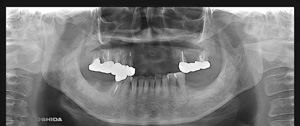

@S.Y‚³‚ñ@ 65Π @’j«@Ž©‰c@@Žèp“ú@‚Q‚O‚O‚W”N@‚UŒŽ‚P‚V“úi‰Îj  ㉺Š{ƒm[ƒxƒ‹ƒKƒCƒhŽg—p@Ö¬“à’ÁÖ@•¹—p

@@@ ㉺Š{  All on ‚U@‘¦Žž‰×d

@    @Rpl Tapered Rp ‚P‚O mm(‚V–{)  @ Rpl Tapered Rp  ‚P‚R mm(‚T–{)@